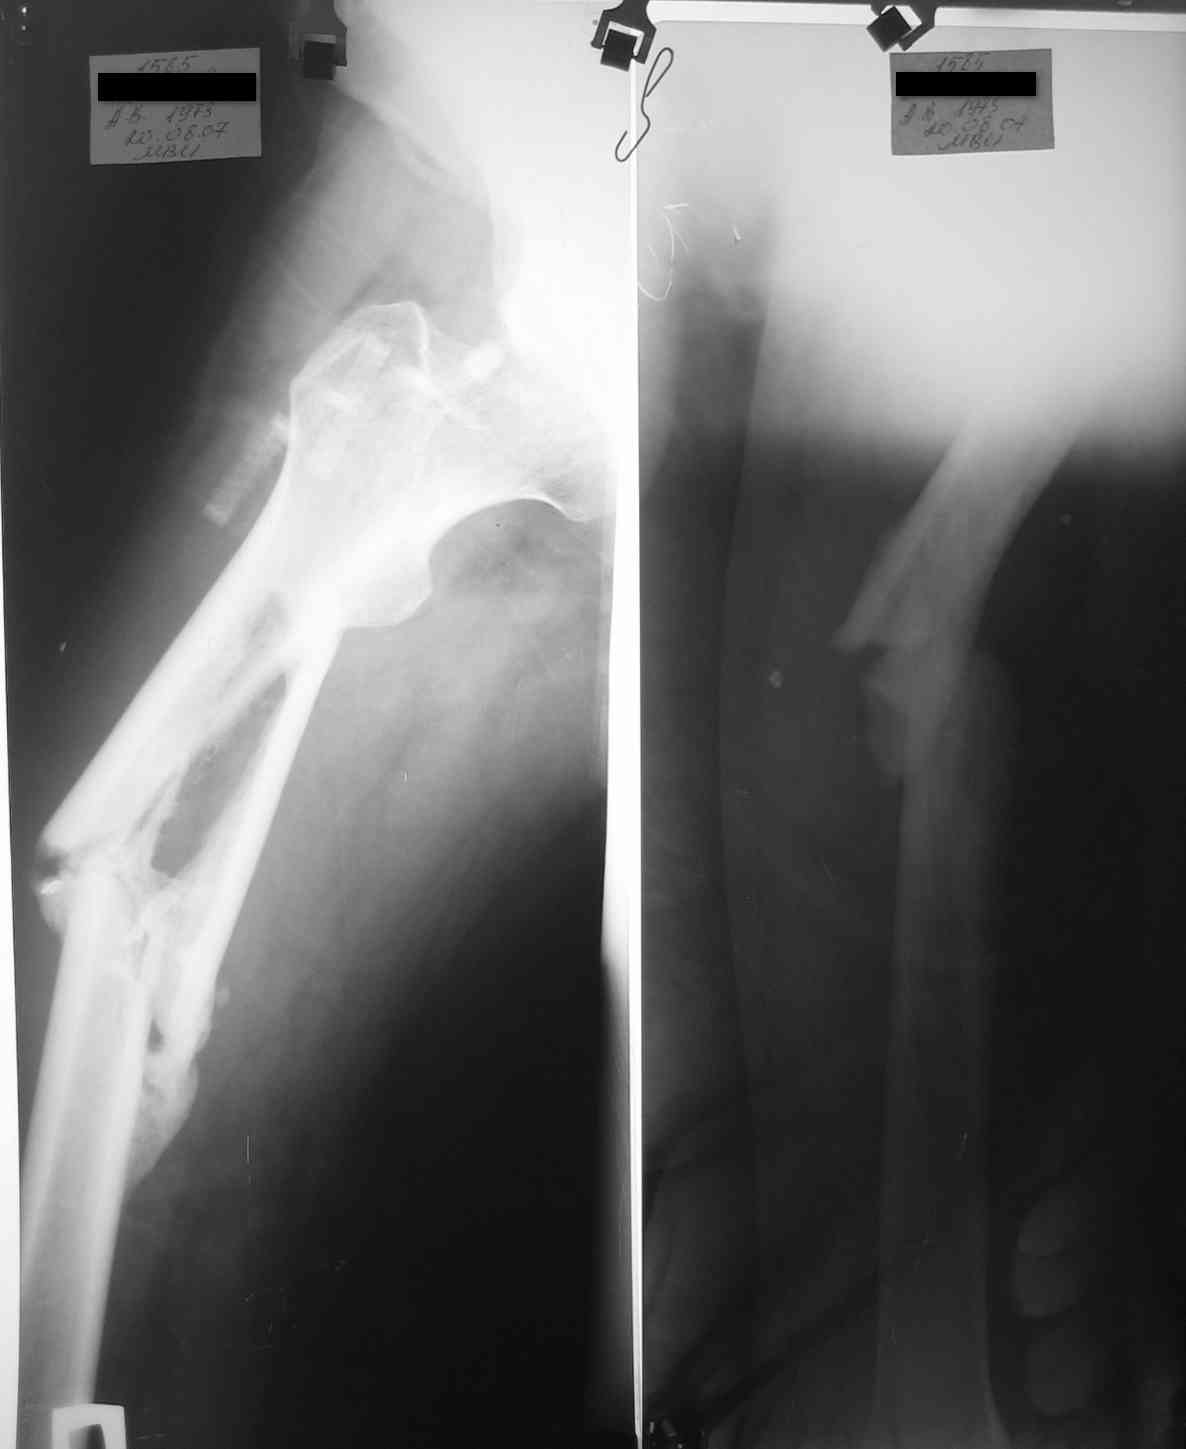

уважаемые коллеги, поступил пациент, через 6 месяцев после травы, который лечлся скелетным вытяжением на районе 3 месяца

затем гипс еще 1,5 месяца, дозированная нагрузка через 3,5 месяца после травмы. Дней 5 назад поскользнулся в ванной, почувствовал боль в бедре, появилась деформация. Оперирован у нас, произведен остеосинтез блокирующим стержнем ,перелом не открывался, был "доломан" на столе. меня интересует вариант вальгирования гвоздя в этом случае. И по-вашему какие ерспективы у этого клиента?

Учитывая отсутствие медиальной стенки на большом протяжении, действительно, мог быть варус при латеральном заходе. Но удалось вполне неплохо справиться, можно поздравить. Из дополнительных мер - точку входа надо делать чуть медиальнее, и можно ввести спицу спереди назад над дефектом, чтобы гвоздь оттеснить к латеральной стенке канала.

Вальгировать (или вальгизировать?) надо не гвоздь, а отломки. Делать это надо, очевидно, при их варусном положении. При последствиях травмы, как в этом случае, изменение положения отломков в любую сторону может быть трудным из-за тугоподвижности. Надо либо их как-то мобилизовать, либо первым этапом устранить угол аппаратом.